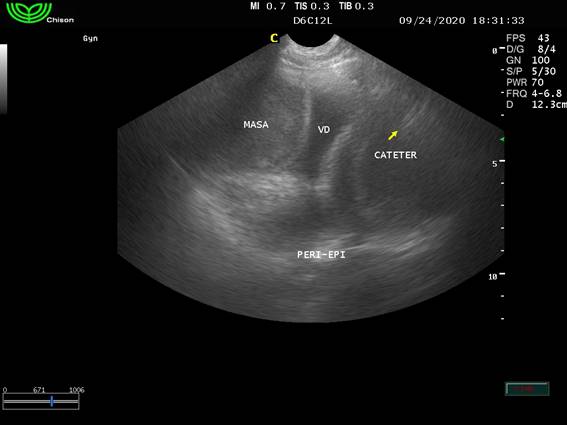

Figura 6: Imagen ecográfica donde se aprecia la masa adherida a la aurícula derecha y se observa el catéter en lateral al ventrículo derecho

Los puntos de sutura se extrajeron a los 14 días, y se controló la evolución de la cicatriz. A los 21 días se extrajo una muestra del líquido y se envió al laboratorio Vetin para la realización de un cultivo bacteriano, el cual se realizó en Agar McConkey y permaneció estéril durante 48 horas. A los 25 días se realizó un control radiológico con triple incidencia para tórax, para comprobar la correcta ubicación del catéter y evaluar metástasis. El estudio radiográfico concluyó en que el catéter rodeaba la zona cardíaca desde caudal a craneal y desde derecha a izquierda. Se evidenció una deformación en el lado derecho cardíaco justo en la zona donde ecográficamente se ubica el tumor. No se evidenciaron metástasis visibles radiográficamente (figura 7).